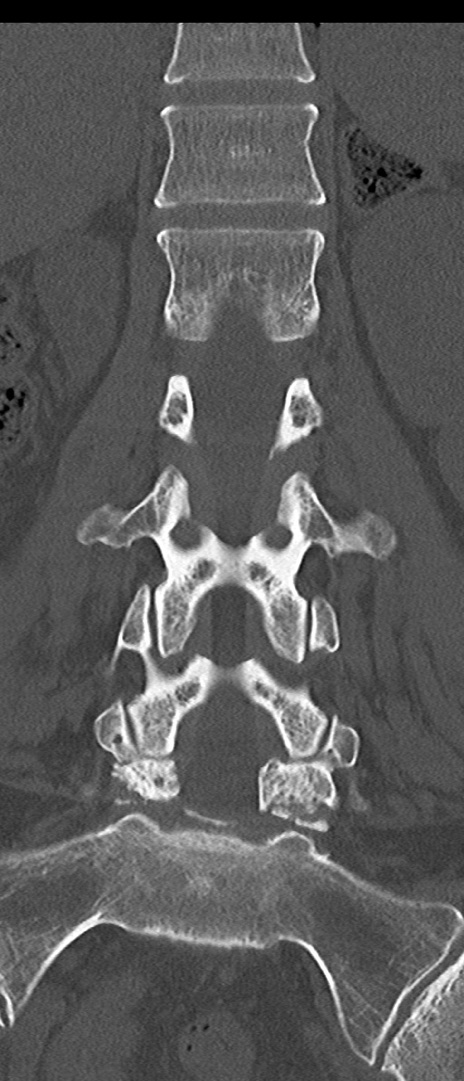

【整形】TIPS症例4 腰椎CT(冠状断像)

腰椎CT